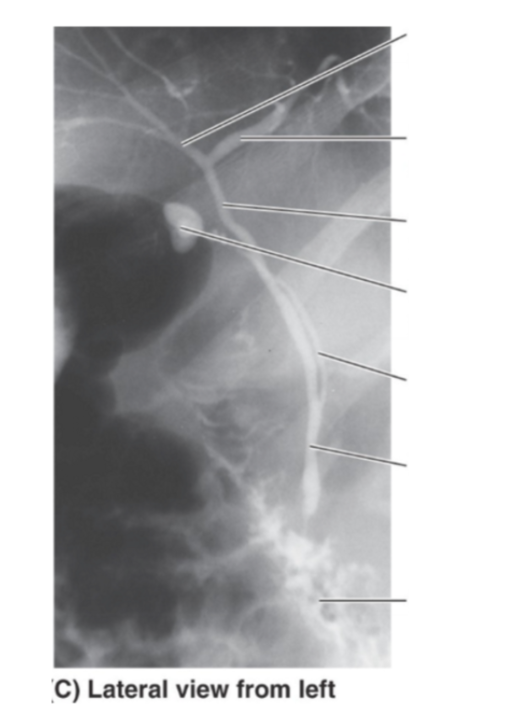

Please label the lateral view of the heart